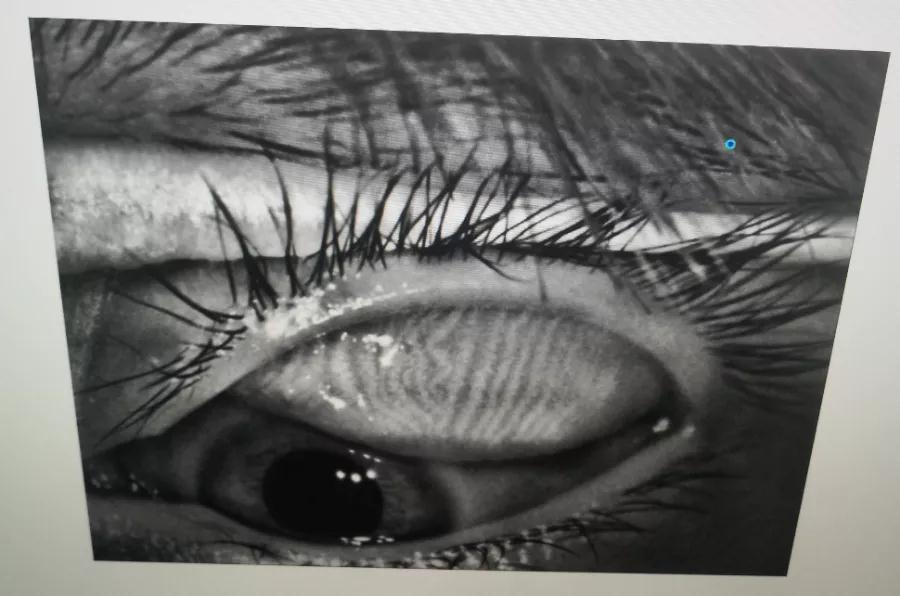

瞼板腺是排列在我們上下眼皮里面,分泌油脂的腺體,這些油脂是組成淚液的重要成分,可以讓淚水更長(zhǎng)時(shí)間的停留在眼球表面。瞼板腺油脂減少,淚水蒸發(fā)就會(huì)加快,眼球暴露在外的時(shí)間變長(zhǎng),會(huì)加重眼睛干澀,時(shí)間一久,干眼也就隨之而來。

通過熱敷并按摩擠壓上下眼瞼,將瞼板腺內(nèi)不能自行排出的分泌物推出,疏通堵塞的瞼板腺開口。

熱敷可以促進(jìn)眼周部位的血液循環(huán),瞼板腺按摩能有效改善瞼板腺功能,解決絕大多數(shù)干眼患者油脂分泌不足問題。

通過強(qiáng)脈沖光高溫消除蠕形螨蟲,同時(shí)脈沖光產(chǎn)生的熱量可以熔解軟化瞼酯,改善瞼板腺內(nèi)脂質(zhì)分泌物的流動(dòng)性,疏通瞼板腺,提高淚膜的穩(wěn)定性,恢復(fù)正常眼表功能和眼部“鎖水”能力,從病因上治療干眼。